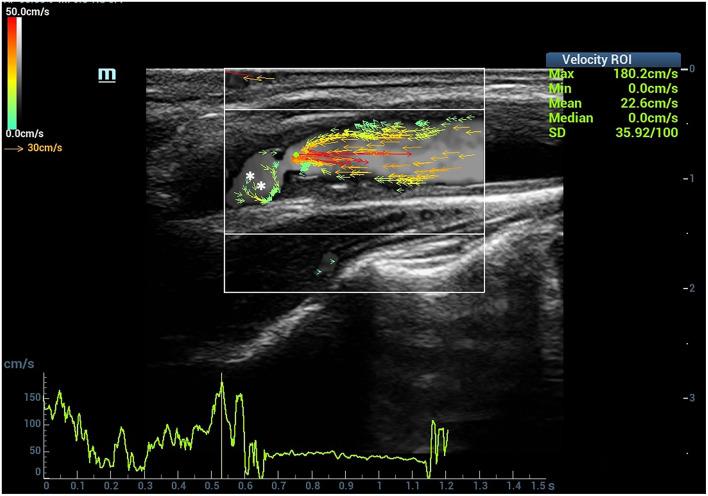

To investigate the value of high-frame rate vector flow imaging technique (V flow) in evaluating the hemodynamic changes of carotid stenosis caused by atherosclerotic plaques. In this prospective study, patients with stenosis rate (diameter) ≥30% caused by carotid atherosclerotic plaques were included. Degrees of carotid stenosis were graded according to North American Symptomatic Carotid Endarterectomy Trial criteria: moderate (30-69%) or severe (70-99%). Mindray Resona 7s ultrasound machine with a linear array transducer (3-11 MHz) was used for ultrasound examinations. The mean WSS value of carotid arteries was measured at the proximal, narrowest region and distal of carotid stenosis. The mean WSS values were correlated with peak systolic velocity (PSV) measured by color Doppler flow imaging and stenosis degree detected by digital subtraction angiography (DSA). The vector arrows and flow streamline detected by V flow dynamic imaging were analyzed. Imaging findings of DSA in carotid arteries were used as the gold standard. Finally, 51 patients were included. V flow measurements were performed successfully in 17 patients (100%) with moderate-grade stenosis and in 30 patients (88.2%) with severe-grade stenosis. Dynamic V flow imaging showed yellow or red vectors at the stenotic segment, indicating fast speed blood flow (up to 260.92 cm/s). Changes of streamlines were detected in the stenotic segment. The mean WSS value measured at the narrowest region of the carotid artery had a moderately positive correlation with stenosis degree ( = 0.58, < 0.05) and PSV value ( = 0.54, < 0.05), respectively. Significant difference was detected in mean WSS value at the narrowest region of the carotid artery between severe carotid stenosis (1.47 ± 0.97 Pa) and moderate carotid stenosis (0.96 ± 0.44 Pa) ( < 0.05). The hemodynamic changes detected by V flow of the carotid stenosis might be a potential non-invasive imaging tool for assessing the degree of carotid stenosis.

探讨高帧率矢量血流成像技术(V flow)在评估动脉粥样硬化斑块所致颈动脉狭窄血流动力学变化中的价值。在这项前瞻性研究中,纳入了颈动脉粥样硬化斑块导致狭窄率(直径)≥30%的患者。根据北美症状性颈动脉内膜切除术试验标准对颈动脉狭窄程度进行分级:中度(30%-69%)或重度(70%-99%)。使用配备线性阵列探头(3-11MHz)的迈瑞Resona 7s超声仪进行超声检查。在颈动脉狭窄的近端、最窄处和远端测量颈动脉的平均壁面切应力(WSS)值。将平均WSS值与彩色多普勒血流成像测量的收缩期峰值流速(PSV)以及数字减影血管造影(DSA)检测的狭窄程度进行相关性分析。对V flow动态成像检测到的矢量箭头和血流流线进行分析。以颈动脉DSA成像结果作为金标准。最终,纳入51例患者。17例中度狭窄患者(100%)和30例重度狭窄患者(88.2%)成功进行了V flow测量。V flow动态成像显示狭窄段出现黄色或红色矢量,表明血流速度较快(可达260.92cm/s)。在狭窄段检测到流线变化。在颈动脉最窄处测量的平均WSS值分别与狭窄程度(r = 0.58,P < 0.05)和PSV值(r = 0.54,P < 0.05)呈中度正相关。重度颈动脉狭窄(1.47±0.97Pa)与中度颈动脉狭窄(0.96±0.44Pa)在颈动脉最窄处的平均WSS值存在显著差异(P < 0.05)。V flow检测到的颈动脉狭窄血流动力学变化可能是评估颈动脉狭窄程度的一种潜在无创成像工具。